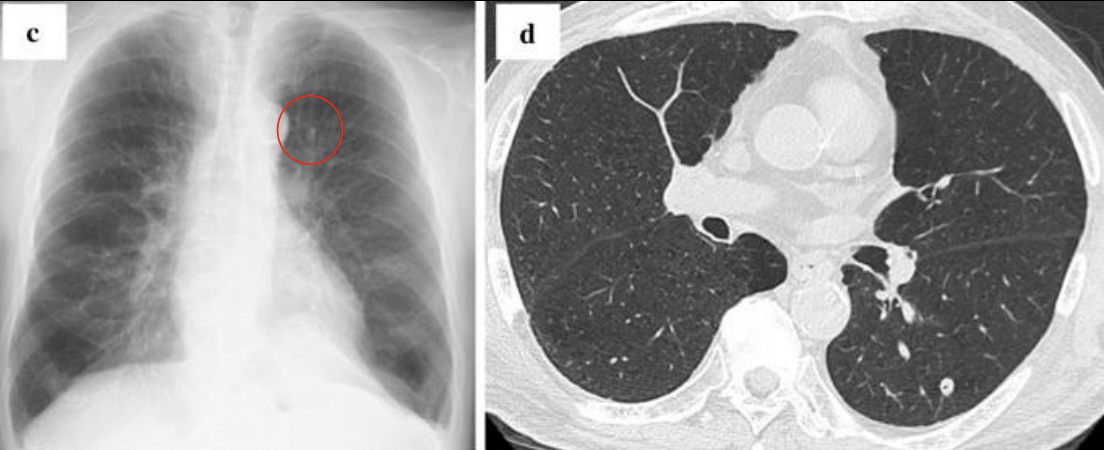

Reactivación: consolidación o parchada o cavitación

Cavitación